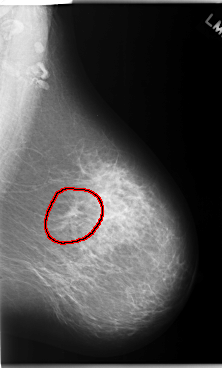

C_0173_1.LEFT_CC

LEFT_CC LINES 5936 PIXELS_PER_LINE 3688 BITS_PER_PIXEL 12 RESOLUTION 50 OVERLAY

FILE: C_0173_1.LEFT_CC.OVERLAY

TOTAL_ABNORMALITIES 1

ABNORMALITY 1

LESION_TYPE MASS SHAPE IRREGULAR MARGINS ILL_DEFINED

ASSESSMENT 5

SUBTLETY 5

PATHOLOGY MALIGNANT

TOTAL_OUTLINES 1

BOUNDARY